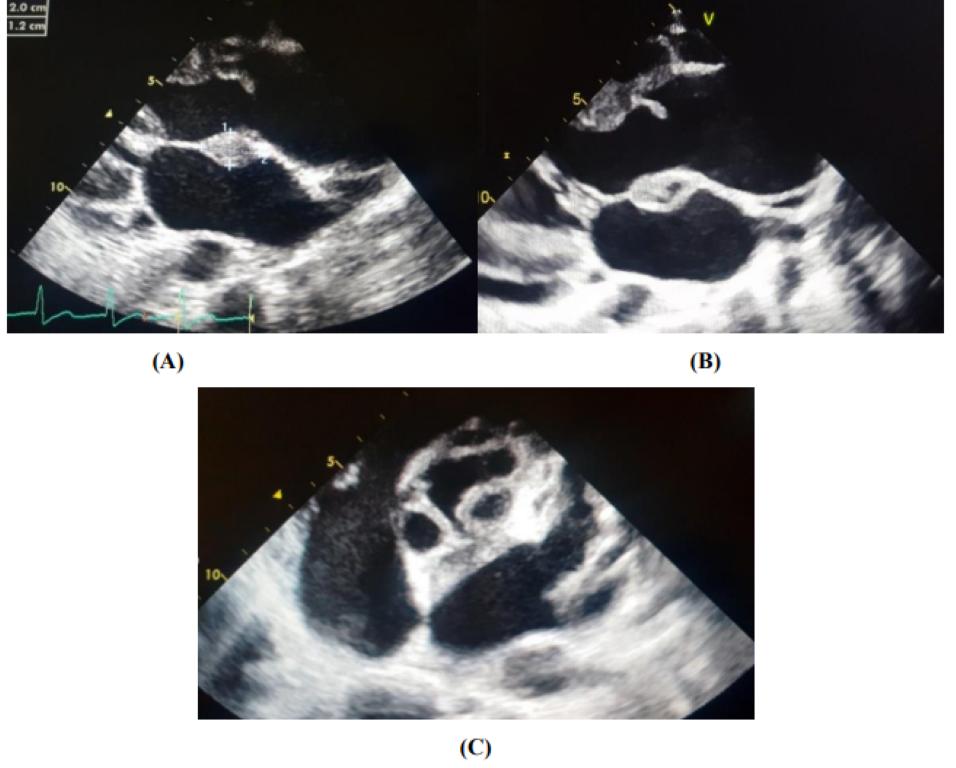

On transthoracic echocardiography, we find an aspect of valvular dilated cardiomyopathy with the presence of 2 vegetations at the level of the aortic valve (Figure 2), severe aortic insufficiency on the bicuspid aortic, and an aneurysmal dilation of the ascending aorta (52 mm), (Figure 3) complicated by an abscess collected at the level of the mitral aorto trigone and a 2nd abscess between the Left and Right cusps of the aortic valve fistulized into the aorta (Figure 4).

Figure 2: Image of two vegetations at the level of the aortic valve [On the ventricular side (A), and another on the aortic side (B)].

Figure 4: Perivalvular abscesses complicating an aortic IE [An abscess collected at the level of the aorto-mitral trigone (A, B) and a 2nd abscess between the Left and Right cusps of the aortic valve fistulized in the aorta (C)]